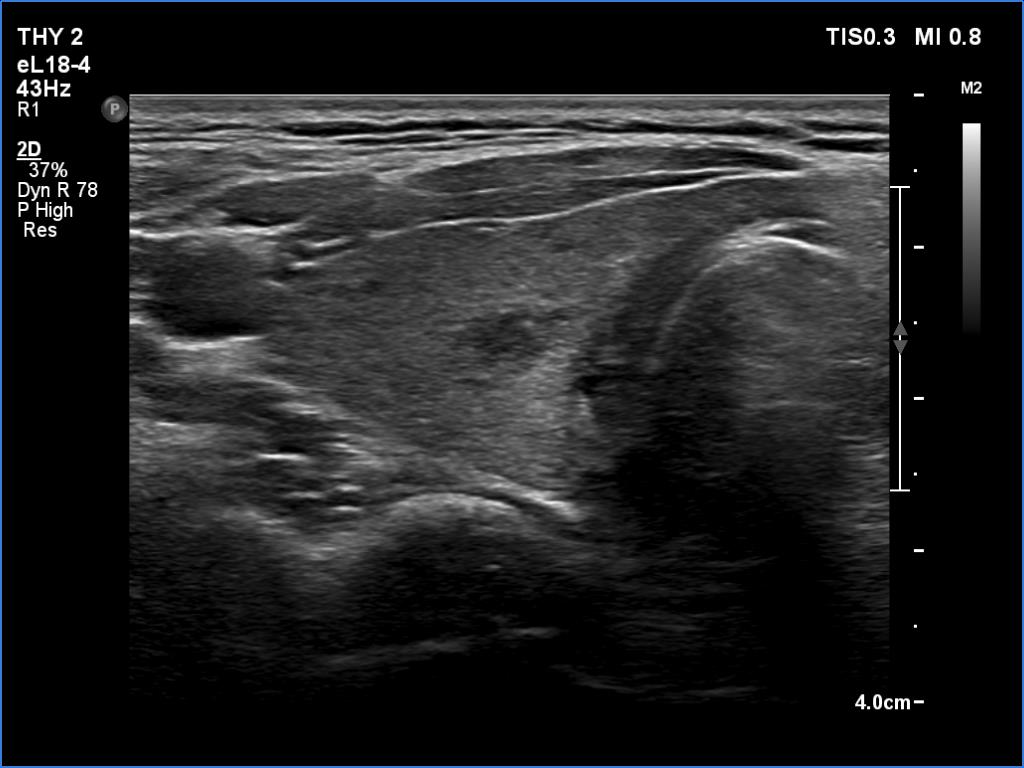

Right lobe, transverse scan

Left lobe, transverse scan